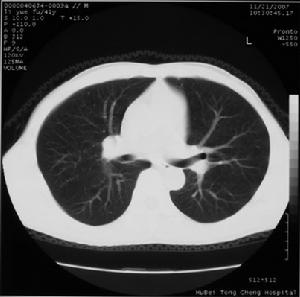

3.第3 期 以咯血為主訴而有胸部病變出現,胸片中可見到局限性結節狀陰影。因為肺動脈瘤是極少見的疾病,又靠近肺門,易將這種病徵性陰影誤認為腫瘤性疾患。咯血可持續數周,終因肺動脈瘤破裂發生大咯血而死亡。

其他輔助檢查:X 線胸片,可見到局限性結節狀陰影。

HUGHES-STOVIN 綜合徵X 線胸片圖診斷為肺部感染和肺淤血的病人在抗感染治療和強心治療後症狀略有緩解,但仍有明顯胸痛、呼吸困難。所有病人在進行溶栓、抗凝治療結合複方丹參液滴注治療後,症狀明顯好轉。胸痛減輕,呼吸困難消失,血氧飽和度升高達100%,3例紫紺病人紫紺症狀消失。6例胸片示實質性病變病人,治療後病灶消失,明顯縮小。肺淤血病人胸片檢查恢復正常。合併下肢靜脈血栓病人,下肢靜脈恢復通暢。所有病人治癒出院。